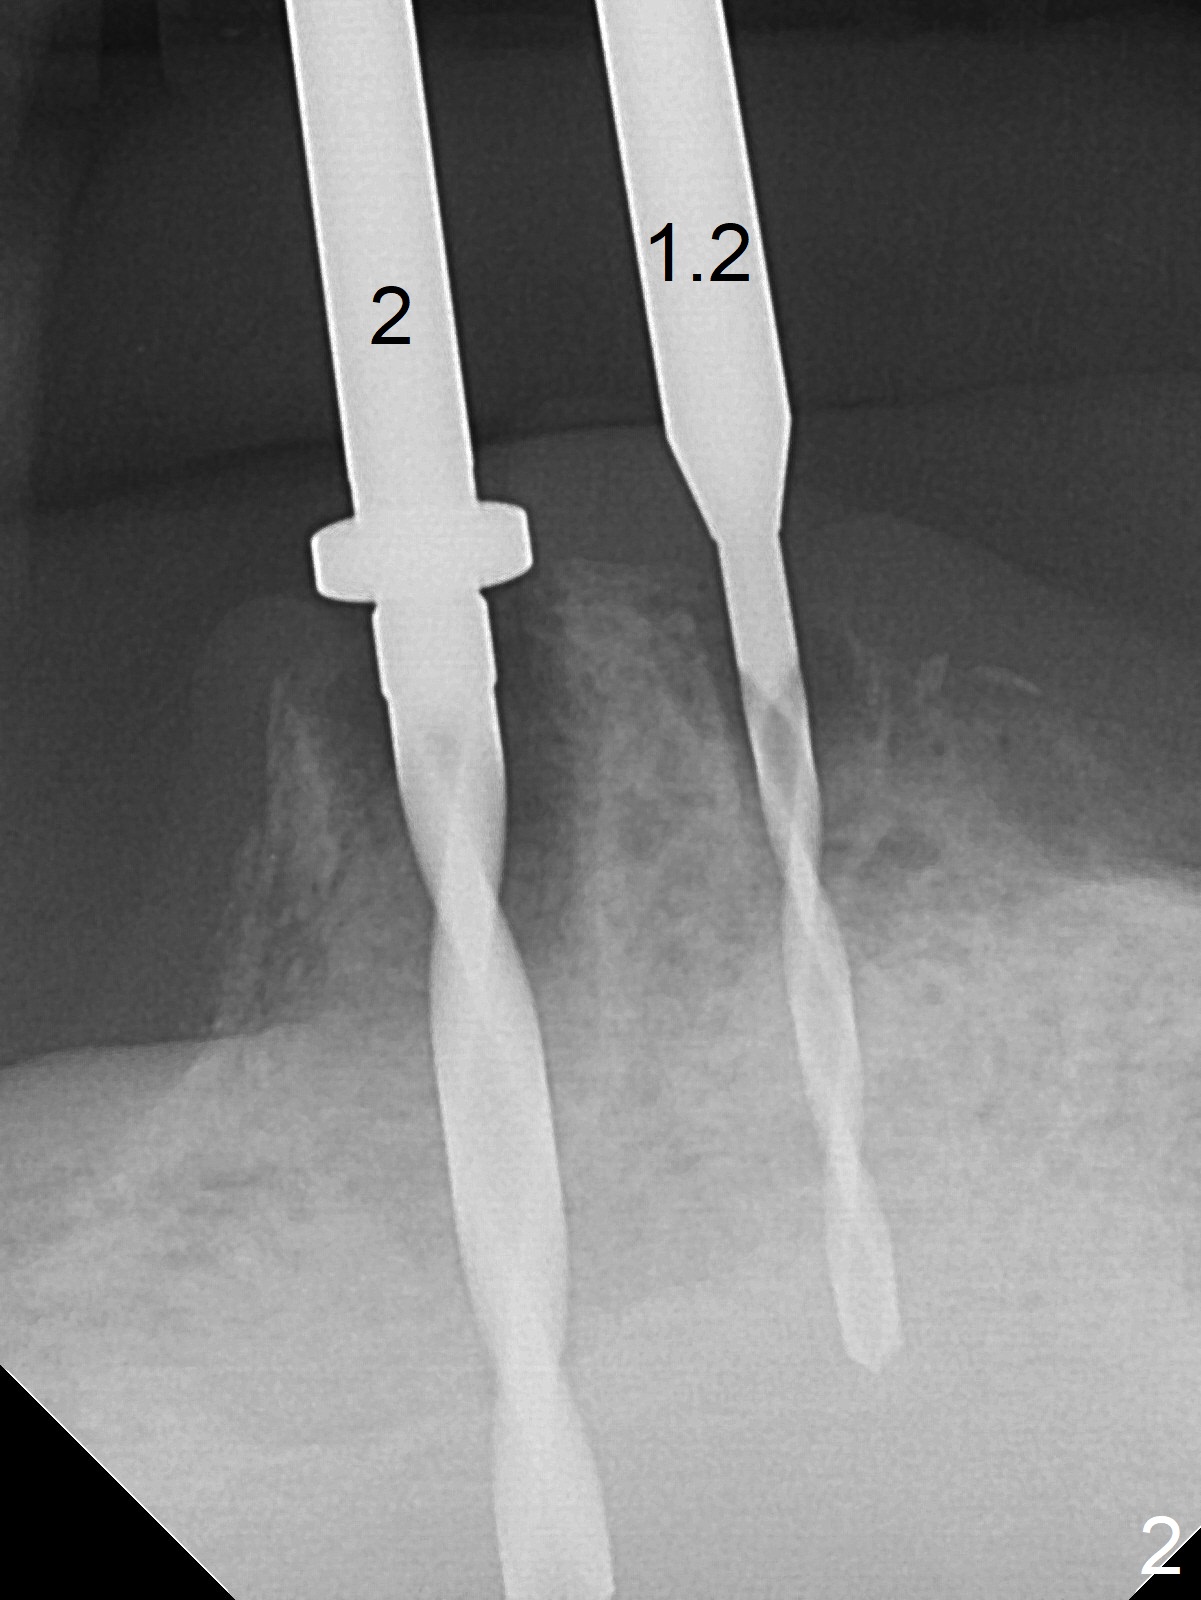

When the patient returns for #26 extraction and immediate implant and #27 RCT, it appears that the tooth #27 with subgingival margin distolingually is non-salvageable (Fig.1). She has dry mouth. Osteotomy is initiated in the lingual slope (Fig.4 red dashed line) of each socket with 1.2 and 2 mm drills for 16 and 19 mm at #26 and 27, respectively (Fig.2,3). The depth at #27 is subsequently reduced, while a 3x14(2) mm dummy implant is placed at #26 (Fig.5,6). A 3.8x13 mm implant is placed at #27 smoothly, while insertion of a 3x16(4) mm definitive implant (by mistake) has resistance (Fig.7). When the depth at #26 increases, there is feeling of perforation. The apex of the implant is truncated prior to reinsertion (Fig.8 >).